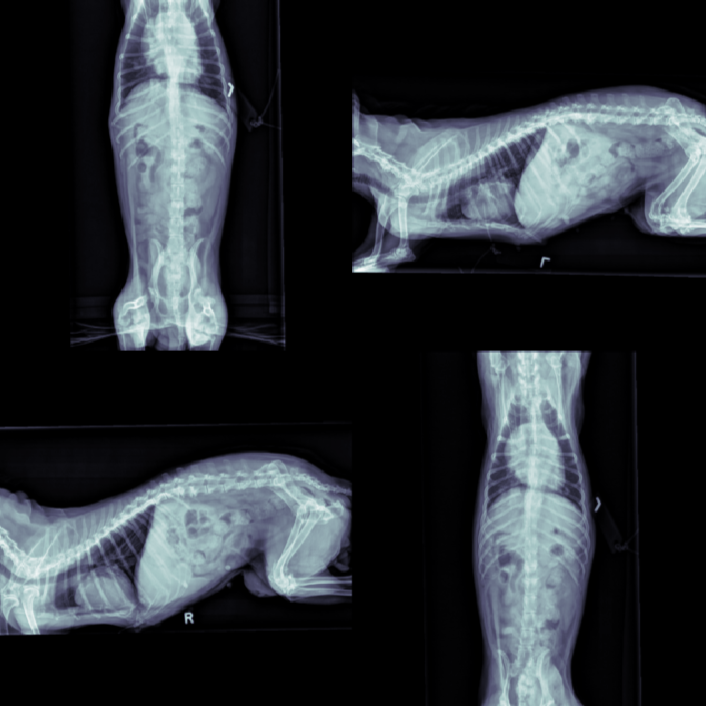

The data for this work consists of 390850 X-ray images, taken from 98660 veterinary sessions. These images were annotated by radiologists for over 41 diseases in a multi-label fashion, and are feedback from the usage of the RapidRead tool. Additionally, we have a dataset of 800 images with high-quality annotations, where the annotations were performed by 12 radiologists collaborating on each image. A sample of these X-ray images is shown in Figure 2.